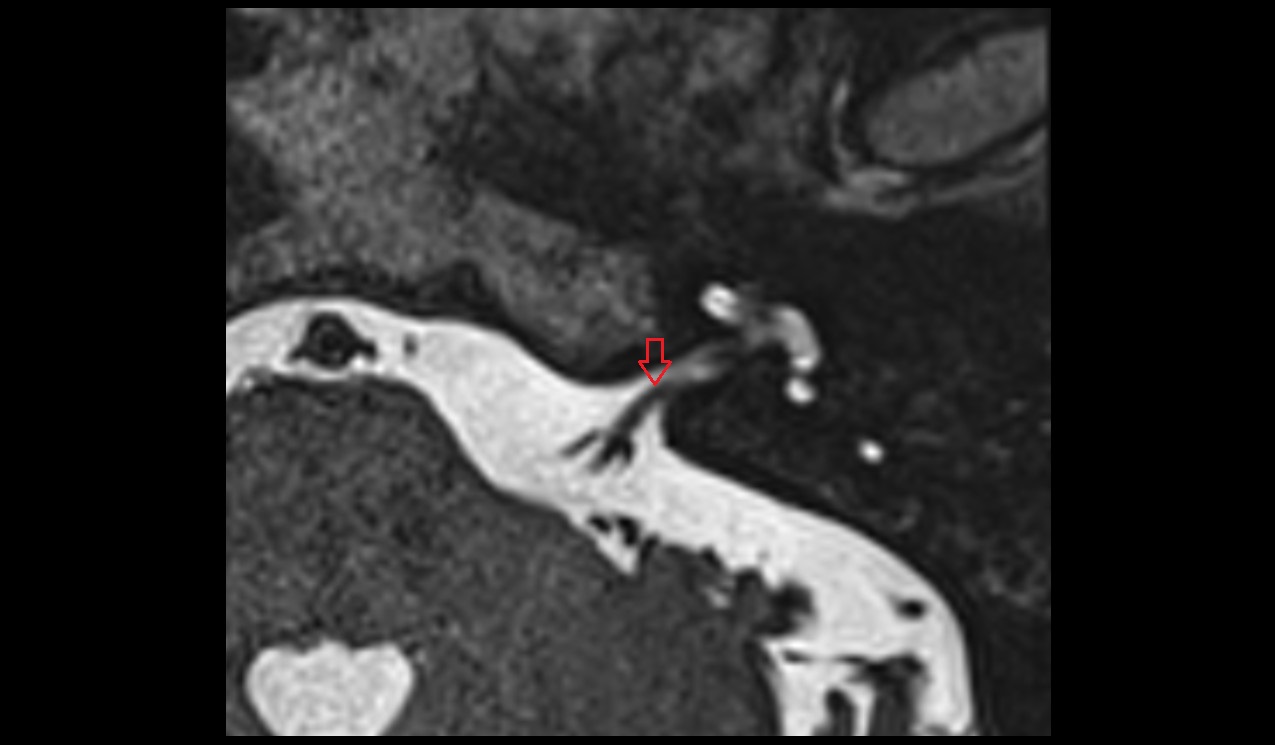

- Articular disc of temporomandibular joint

- Temporomandibular joint